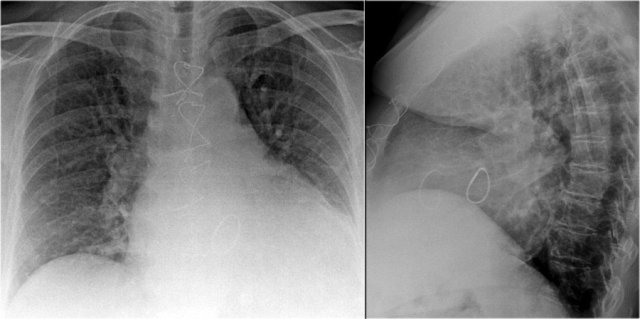

Old films

It is extremely important to always compare with old films, as we will demonstrate in this case.

Actually someone said that the most important radiograph is the old film, since it gives you so much information.

For instance a lung mass, which hasn't changed in many years is not a lung cancer.

First study the chest films.

Based on these films, you could make the diagnosis of congestive heart failure, but the findings are subtle.

Continue with the old film...

Scroll back and forth to the old film.

Once you compare the chest film to the old one, things become more obvious and you will be much more confident in your diagnosis of congestive heart failure:

- The size of the heart is slightly increased compared to the old film, but was already large on the old film.

- The pulmonary vessels are slightly increased in diameter indicating increased pulmonary pressure.

- There are maybe some subtle interstitial markings as a result of interstitial edema.

- There is pleural fluid bilaterally. Notice that the infero-posterior border of the lower lobes has changed in position.